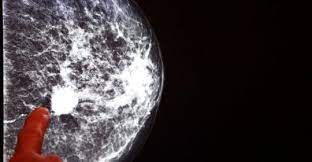

Rata de supraviețuire depinde, de asemenea, de localizarea cancerului și stadiu. Deoarece cancerul de san nu poate fi prevenit, singura. Stadiul in care este cancerul este o informatie esentiala pentru a se decide tratamentul potrivit.

De aceea este foarte important de stiut ce stadiu are cancerul tau. Care sunt stadiile cancerului de san. Stadiul iv sau cancerele de san metastatice au o rata de supravietuire de 5 ani de aproximativ 22%.

Cancerul la sân are mai multe stadii, cuprinse intre 0 si iv, iar pentru depistarea si începerea tratamentului sunt necesare o serie de teste.

Cancerul de san este o tumora maligna care debuteaza la nivelul celulelor sanului. Rata de supraviețuire depinde, de asemenea, de localizarea cancerului și stadiu. Când cancerul este localizat doar în sân, rata la 5 ani este de 99%, și 62% dintre femei sunt diagnosticate în acest stadiu.